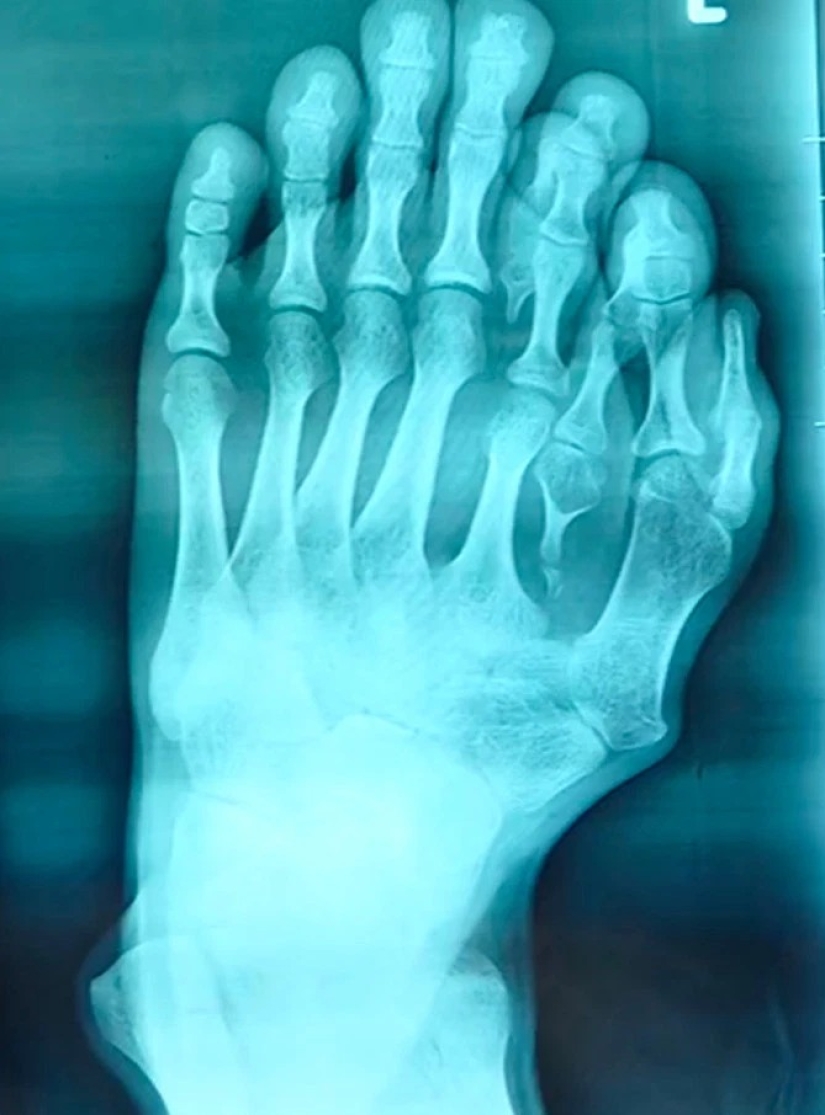

By Pictolic https://www.pictolic.com/article/happiness-is-never-too-much-the-chinese-have-long-lived-with-14-toes-considering-the-anomaly-of-happy-sign.htmlThe man who was born with four extra fingers on the left leg, and thought about surgery to get rid of them, because his parents believed this anomaly sign of good luck. Only recently, 21-year-old Chinese man was operated on, giving the ability to wear shoes and to find happiness in his personal life. Find out how the guy lived with a rare deviation from our article.

The parents of 21-year-old Chinese by the name of Azzun believed that four extra fingers on my left foot the son is a sign of good fortune. The young people anomaly brought a lot of inconvenience in daily life, as well as physical suffering: in ten years he stopped wearing sandals because of the bleeding wounds on his legs.

When Azzouni matured, he turned for advice to the surgeons in the hospital Surgical Shunde Heping Hospital of Foshan city. His doctor At Xiang (Xiang Wu) said that such operations are doing in in childhood, so the 21-year-old patient was a special case.

The doctor says that children who are born with such disabilities need to operate up to six years before they go to school. This is important for the psychological state of the child, and to accelerate the process of recovery and adaptation.The young man believes that his life will finally get better. He hopes to meet a girl that will be happy. The guy is very grateful to the surgeons for giving him the opportunity to be normal. Superstition parents almost destroyed the life of Assuna, but common sense prevailed, and now the guy has a chance for a better future.